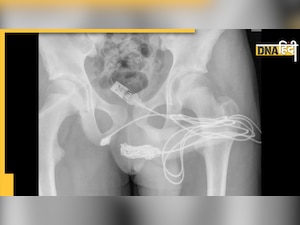

हुआ यूं कि एक 15 साल के लड़के को गंभीर हालत में अस्पताल में एडमिट करवाया गया. लड़का दर्द से कराह रहा था. पूछने पर उसकी मां ने बताया कि उनके बेटे को पेट में काफी दर्द महसूस हो रहा है. इसके अलावा उसके प्राइवेट पार्ट से भी लगातार खून आ रहा था. जब वो टॉयलेट करता तब स्थिति और दर्दनाक हो जाती. यह देख डॉक्टर्स ने बिना देरी किए लड़के का एक्सरे किया. अब जब एक्सरे की रिपोर्ट आई तो हर कोई हैरान रह गया. लड़के के पेट के अंदर एक यूएसबी वायर था.

वायर उसके यूरेथा के पास जाकर जमा हो गया था और तार में कई गांठें पड़ गई थी. आप सोच रहे होंगे कि मोबाइल चार्ज करने वाला ये केबल लड़के के पेट में कैसे पहुंचा. इसके पीछे कि वजह आप जानेंगे तो खुद ही अपना सिर पीट लेंगे. दरअसल, डॉक्टर्स लगातार लड़के से इस वायर के बारे में पूछ रहे थे और लड़का कुछ भी कहने को राजी ही नहीं था. बाद में जब उसकी मां कमरे से बाहर गई तब जाकर उसने इसके पीछे का राज खोला.

लड़के ने डॉक्टर्स से बताया कि वो अपने प्राइवेट पार्ट की लंबाई अंदर से नापना चाहता था. इसके लिए उसने खुद ही तार को प्राइवेट पार्ट के अंदर डाला था लेकिन ऐसा करने के दौरान उसके हाथ से तार का सिरा छूट गया और पूरा तार अंदर चला गया. उसने इसे बाहर निकालने की भी काफी कोशिश की लेकिन तार के अंदर गांठें पड़ गई थी. इस वजह से तार को खींचने पर केवल दर्द हो ही रहा था.

लड़के के मुंह से इस तरह की बातें सुनने के बाद डॉक्टर्स का भी सिर चकरा गया. बाद में उन्होंने तुरंत उसका ऑपरेशन किया और तार को बॉडी से बाहर निकाला. इसके बाद लड़के को कुछ दिन के बाद डिस्चार्ज कर दिया गया.